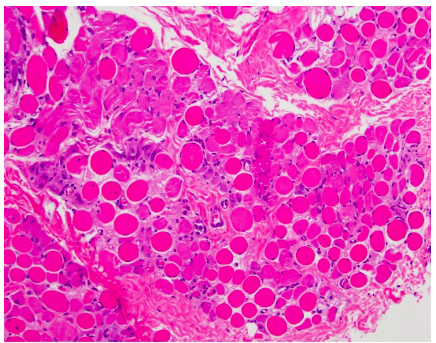

Purkinje fibers

Purkinje Fiber

Involuntary innervation by autonomic nervous system

Pacemaker system of modified cardiac muscle cells that generate and coordinate myocardial contractions during cardiac cycle (Purkinje system)